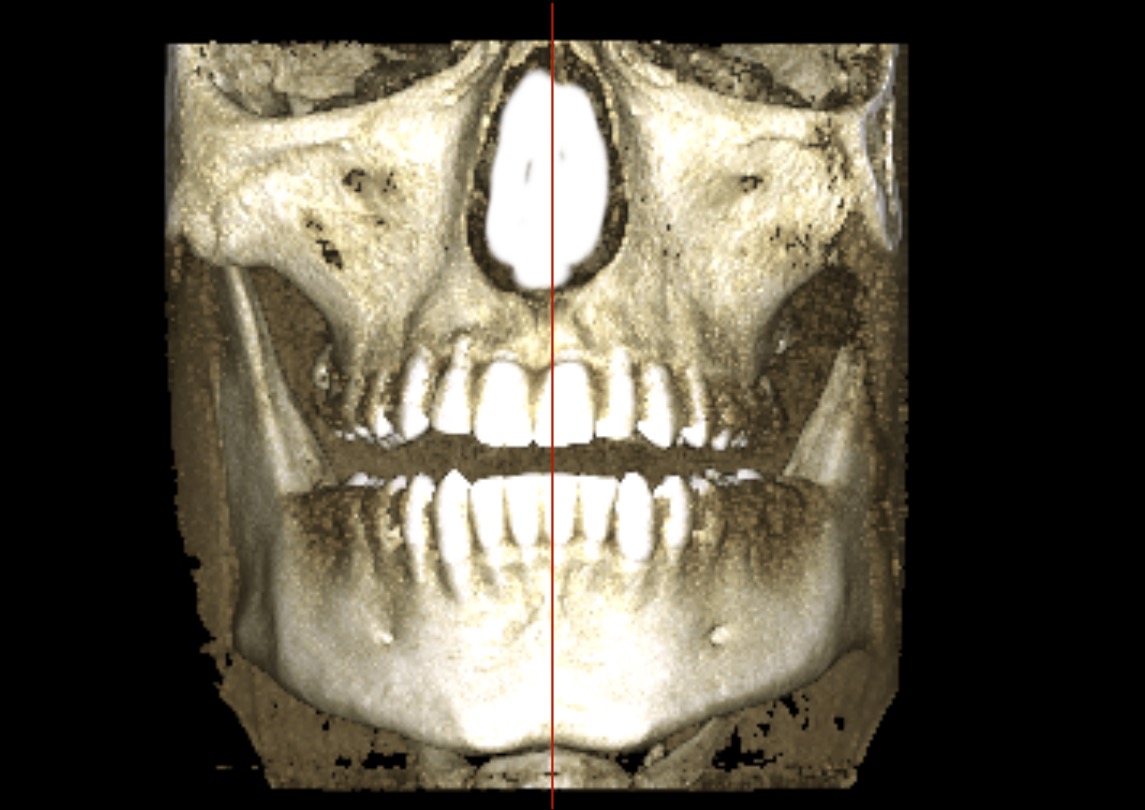

This is how it looks when i try ( and fail) to edit the midline towards center of the face

IMG 4806

seems to be centered, it's just the alveolar bone playing tricks with you head, your teeth are a lil overcrowded and the "midline" in the teeth has "shifted" (thankfully because of the xray you can see that with braces a clear aligner or even a toothborne expander you could fix your overcrowded lower teeth and move the "mid-line" to the right spot, your occlusion doesn't follow the "guide lines" of the bones also I notice that the upper jaw seems to be inlign with the "midline"(teeth and the base of the nasal cavity as you can see in the image)

The alveolar bone in the upper jaw seems to be shifted